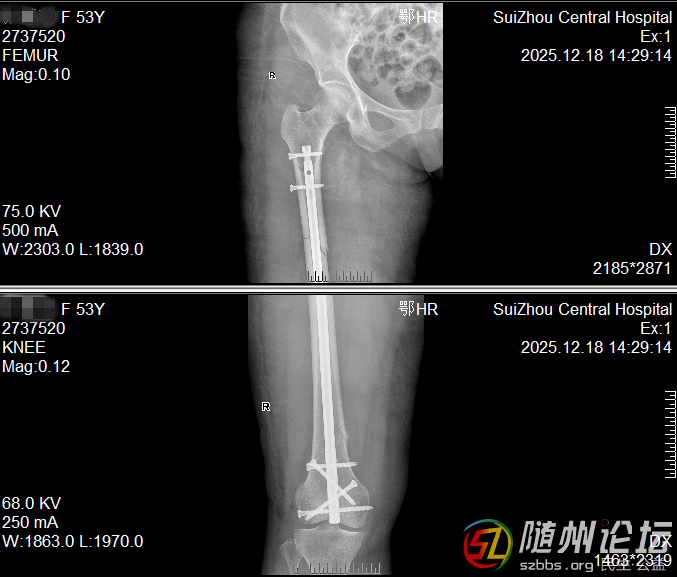

大腿多段骨折,一個小口完成修復

一位53女士大腿多處骨折,甚至影響到膝蓋。我們僅在膝蓋上方開一個約4厘米的小口,放入一根髓內釘將骨折處全部連接固定。這樣既保護了腿部血流和肌肉,也為后期膝蓋活動打下了好基礎。